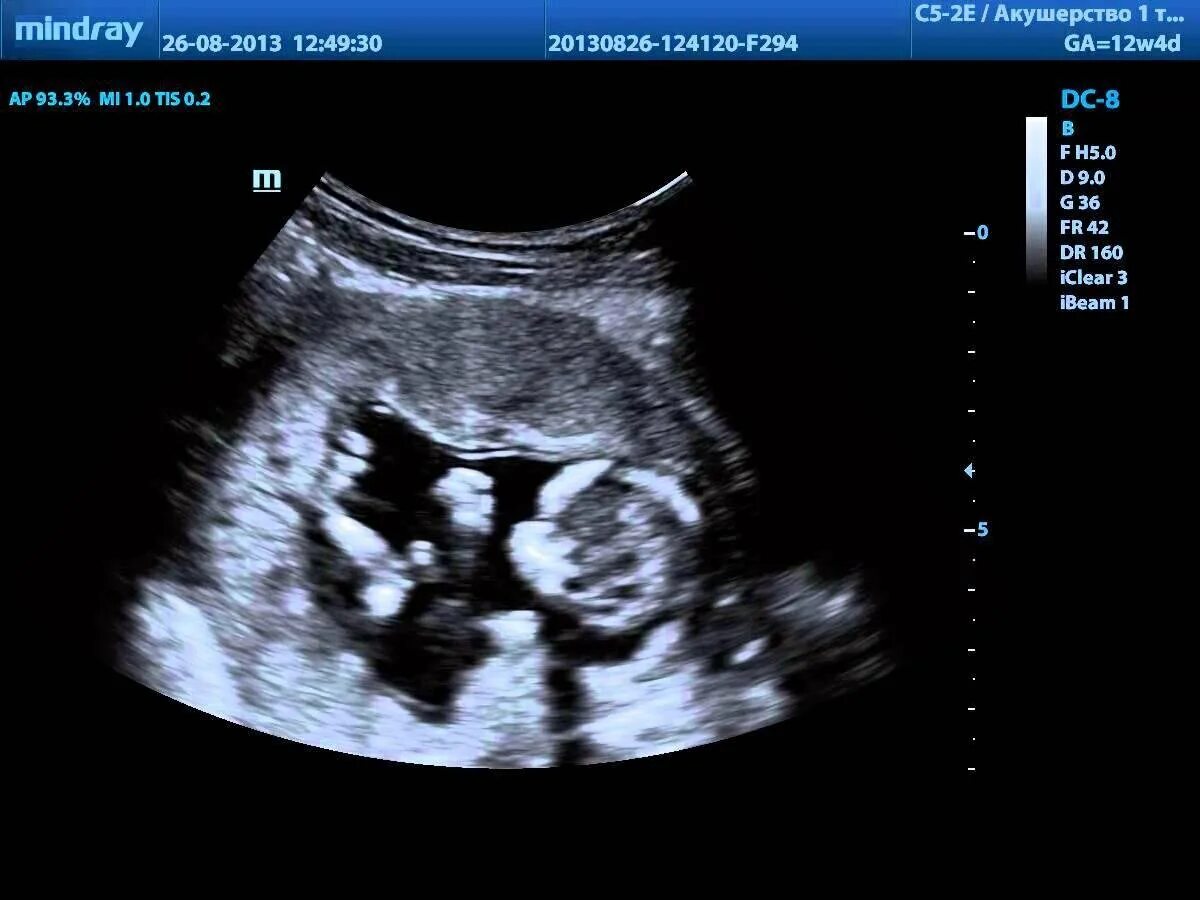

Что смотрят на 1 узи